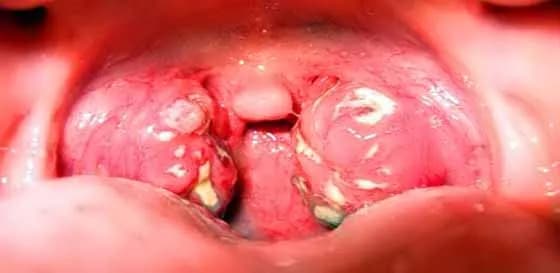

Angina, znana również jako zapalenie migdałków, to powszechna choroba, która może występować w różnych formach. Wyróżniamy trzy główne rodzaje anginy: anginę bakteryjną, anginę wirusową oraz anginę grzybiczą. Każdy z tych typów różni się przyczynami oraz objawami, co ma istotne znaczenie dla diagnostyki i leczenia.

Choć angina grzybicza jest znacznie rzadsza, może wystąpić u osób z osłabionym układem odpornościowym. Infekcje grzybicze mogą prowadzić do stanu zapalnego migdałków, co powoduje ból i dyskomfort. Osoby takie często mają trudności z połykaniem, a objawy mogą być mylone z innymi formami anginy.

Diagnostyka anginy bakteryjnej opiera się głównie na badaniach laboratoryjnych, które potwierdzają obecność bakterii. Objawy mogą obejmować intensywny ból gardła, gorączkę i powiększenie migdałków. Leczenie anginy bakteryjnej polega zazwyczaj na stosowaniu antybiotyków, które są skuteczne w eliminacji bakterii.